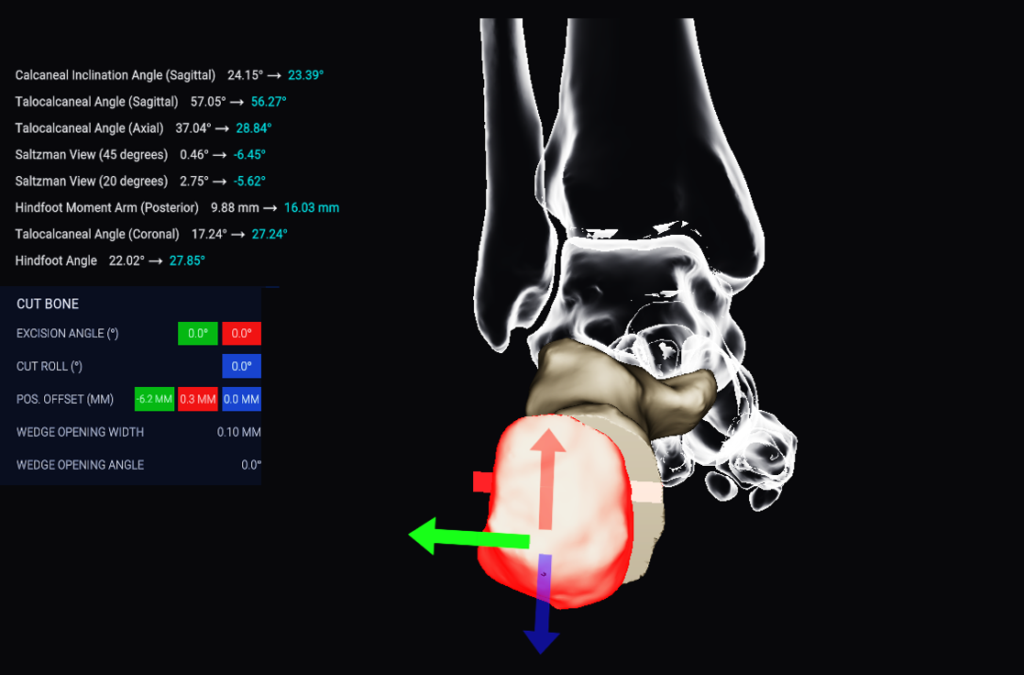

Disior®’s new Bonelogic® Planning module is quick and easy-to-use software that supports you to plan orthopedic treatments of the hand or foot. This product can be purchased together with the Hand & Wrist or Foot & Ankle modules to give you complete control over your clinical workflow.

3D treatment planning in minutes, saving you time in the operation room

Live bone alignment analytics* that help support your decision making

*Note that the live bone alignment measurement values do not reflect any influence that the soft tissue may have.